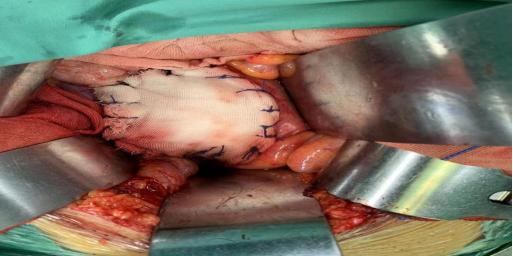

置入隔离物大纱垫

重(碳)离子治疗靶区勾画,瘤体与危及器官间手术置入隔离组织物,为目标肿瘤与周围正常组织提供了足够的距离,从而可以给肿瘤以充足的根治剂量。

手术将肿瘤与肠管间置入纱扩垫,隔开肠管,保护肠管,当天完成重离子灭活肿瘤